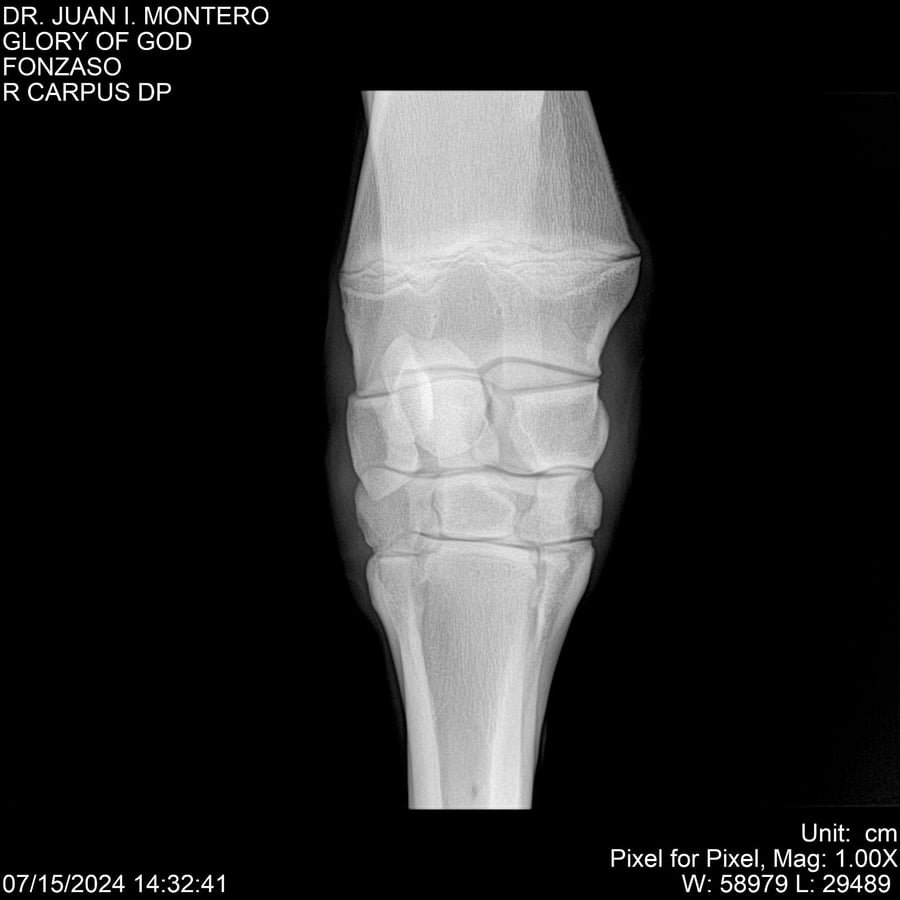

LOTE 10, GLORY OF GOD 🔥 🔥 🔥 Lote Anterior Volver al remate Lote Siguiente Ficha Contacto Montevideo - Ficha del Lote Identificador: #281389 Categoría: Yeguarizos Montevideo - 115 Visualizaciones ClicData Contacto Empresa: Abelenda N. R., Walter Hugo Nombre*: Teléfono* : E-mail* : Mensaje Enviar Registrese gratis Este contenido Exclusivo está disponible sólo para usuarios registrados Ingresar